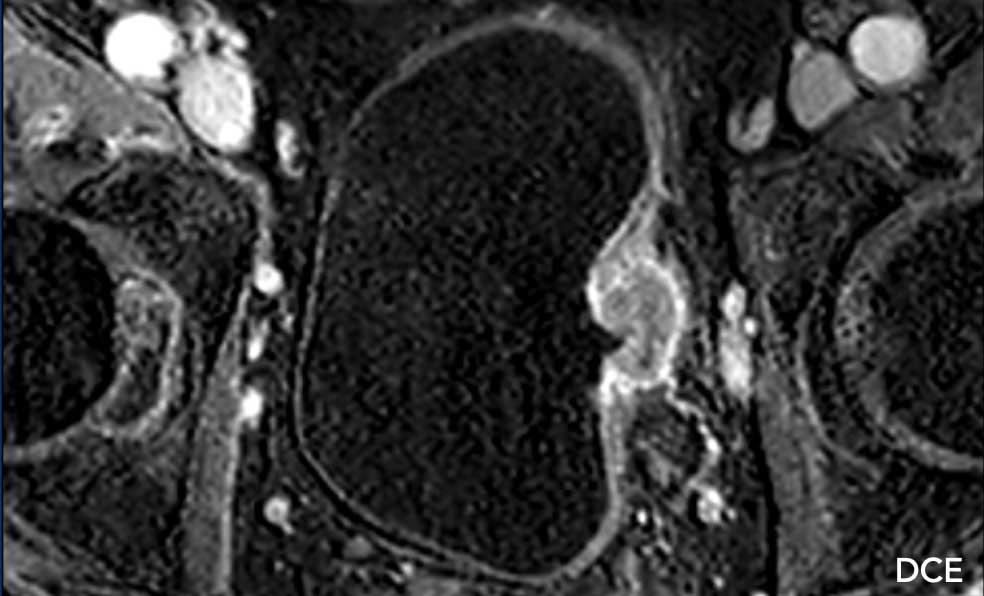

DCE

Có ngấm thuốc sớm của khối u xâm lấn vào mỡ trước bàng quang.

DWI/ADC

Tổn thương xâm lấn mỡ quanh bàng quang tăng tín hiệu trên chuỗi xung DWI, trong khi giảm tín hiệu trên chuỗi xung ADC.

Kết luận

T2W 5, DCE 5, DWI/ADC 5.

Điểm VI-RADS cuối cùng: 5